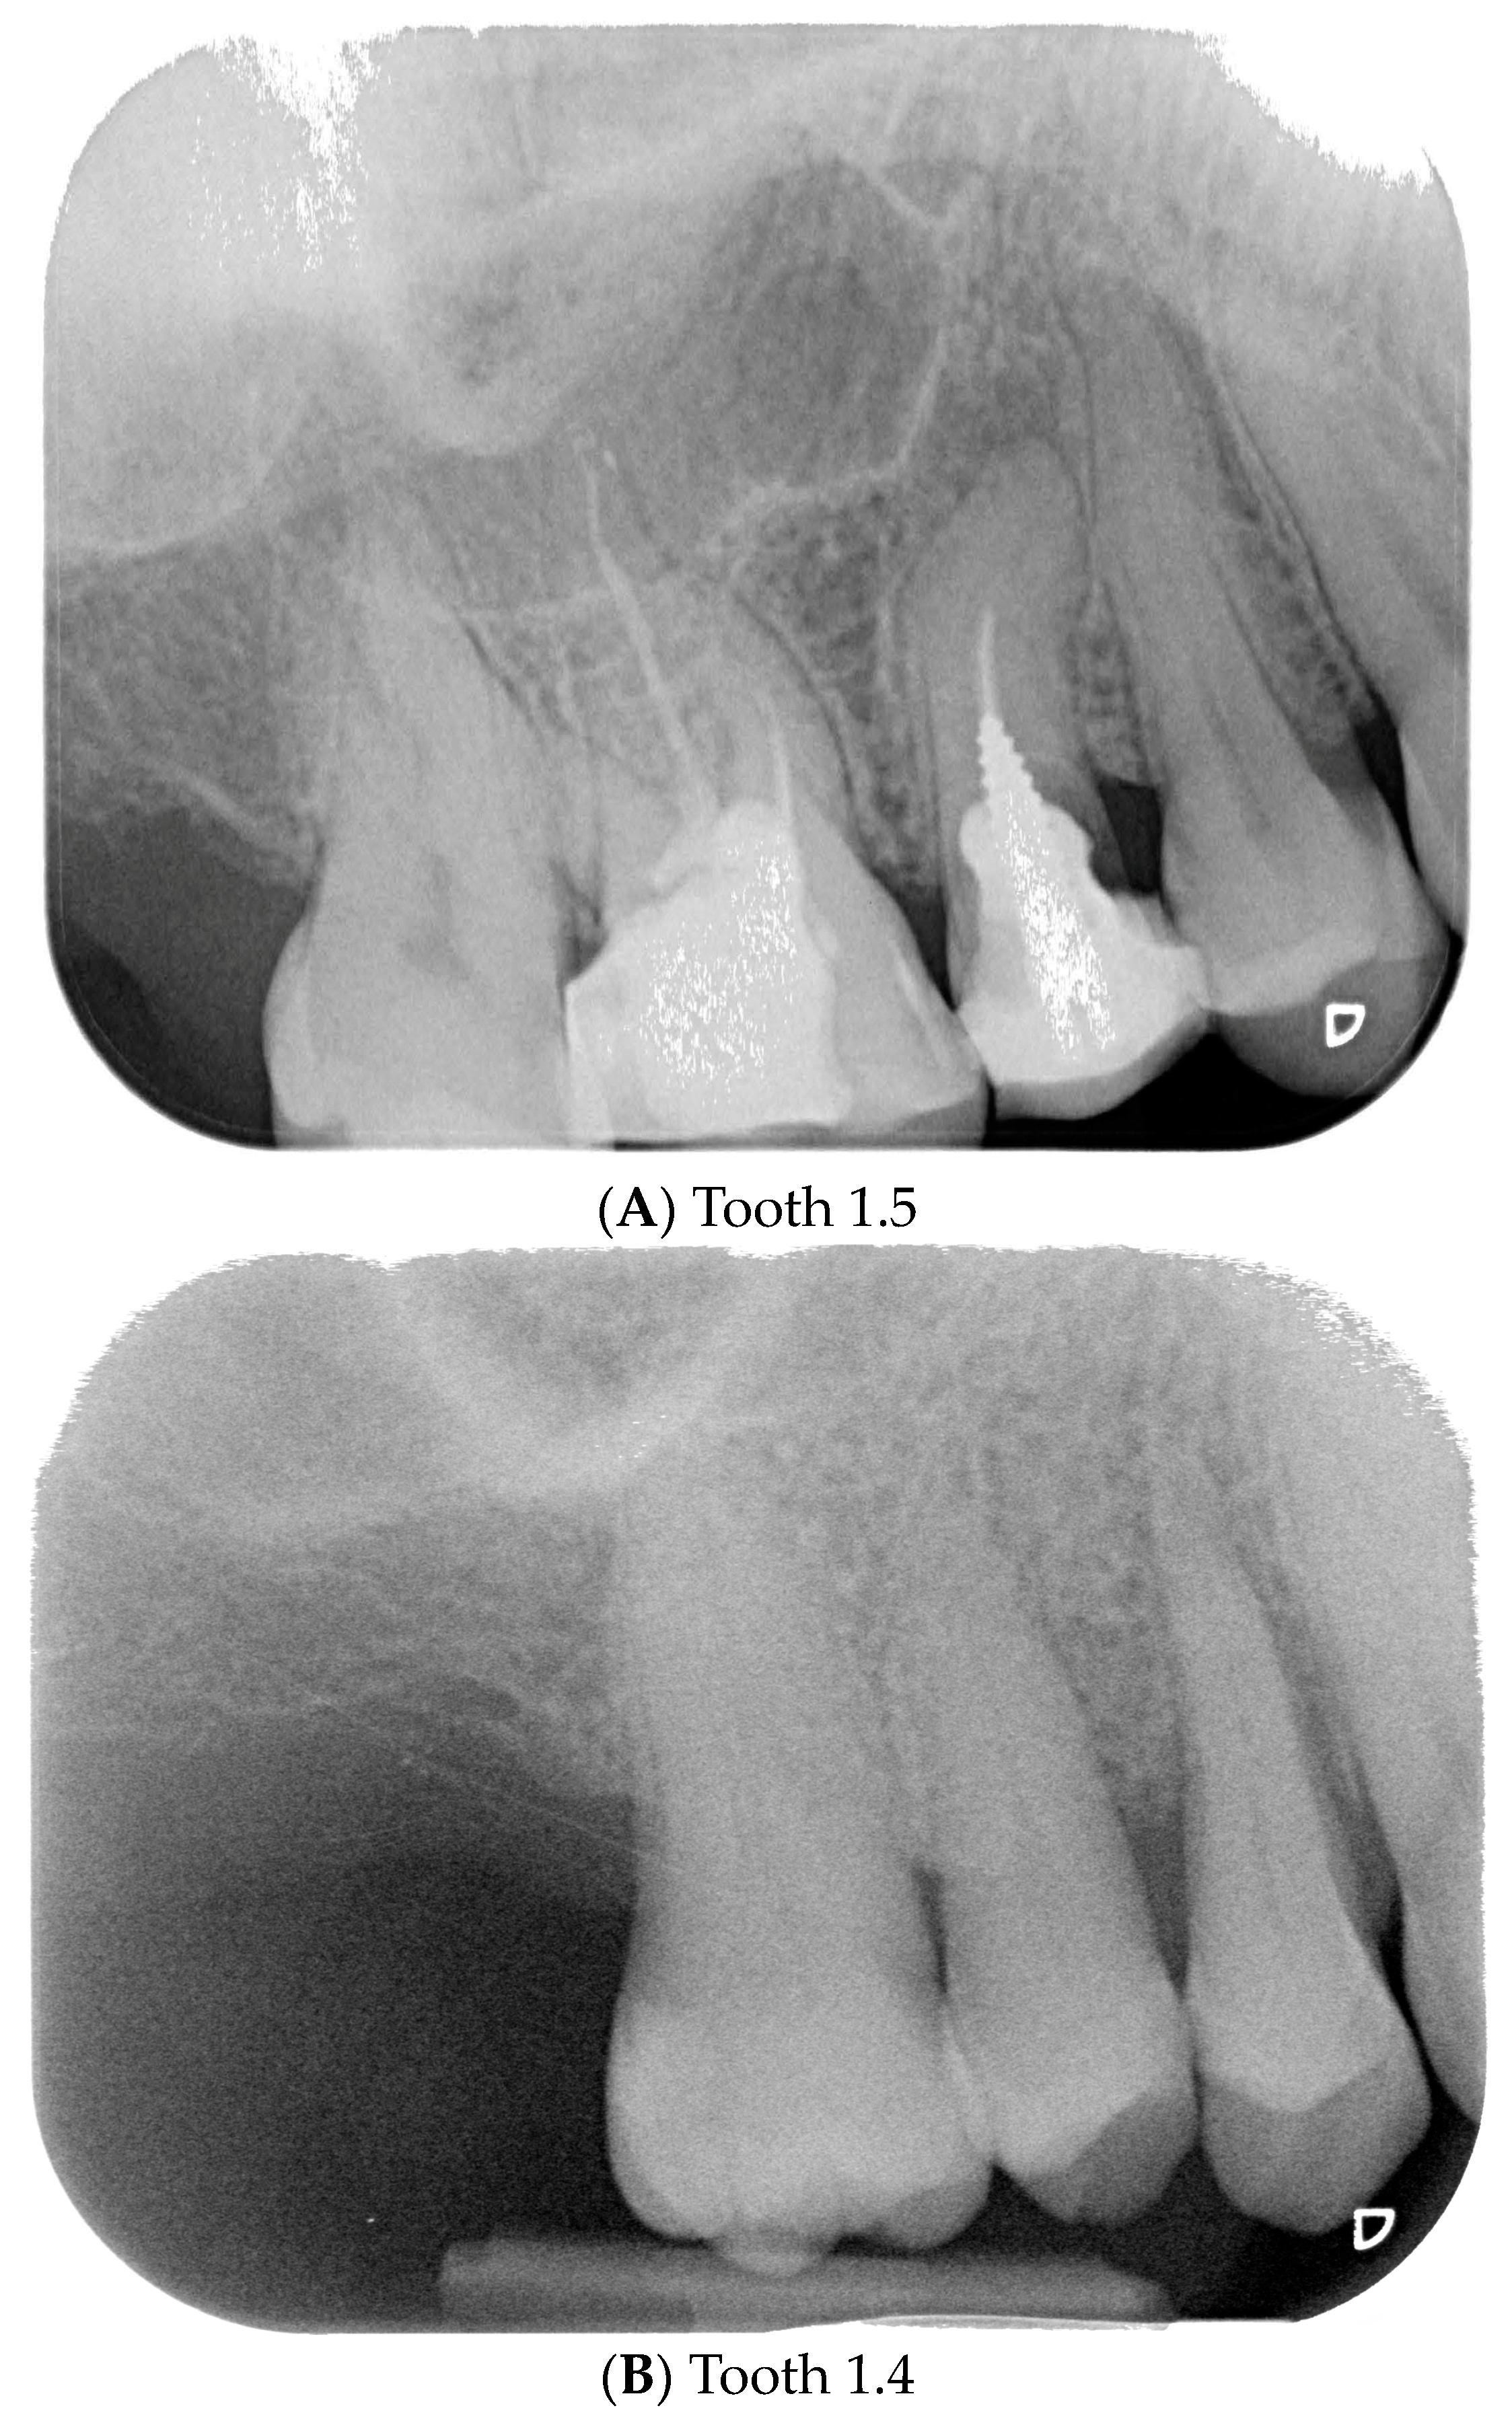

The primary outcome measure was the maintenance of peri-implant soft tissue architecture over a period of five years, assessed by measuring the distance between the peri-implant soft tissue margin (defined as the gingival and peri-implant connective tissue) and the implant fixture surface (defined as the surface of the implant that is surgically placed into the jawbone) at baseline (T0), three months (T1), one year (T2), and five years (T3). T0 represents the situation after the implant insertion. Upper premolars (teeth 1.4 and 1.5) and molars (teeth 1.6 and 1.7) designated for extraction had ≥5 mm apical bone, ≥12 mm height, ≥5.5 mm alveolar bone thickness, and D2 or D3 bone quality (Misch classification). Teeth lacking vestibular/palatal cortical bone, with periapical/periodontal lesions, or Class B/C (Tarnow classification) were excluded (Figure 1, Figure 2 and Figure 3A).

Figure 3.

Endoral RX prior to implant insertion: test group (A) vs. control group (B).

Preoperative examination addressed smile line, inter-arch relationship, and bucco-lingual bone thickness. Periapical radiographs and cone beam computed tomography (CBCT) were obtained to assess root dimensions, bone availability, adjacent structures, and implant planning. Preoperative periapical radiographs were taken using the VistaScan Mini Plus device (Figure 3) (Dürr Dental SE, Bietigheim-Bissingen, Germany).